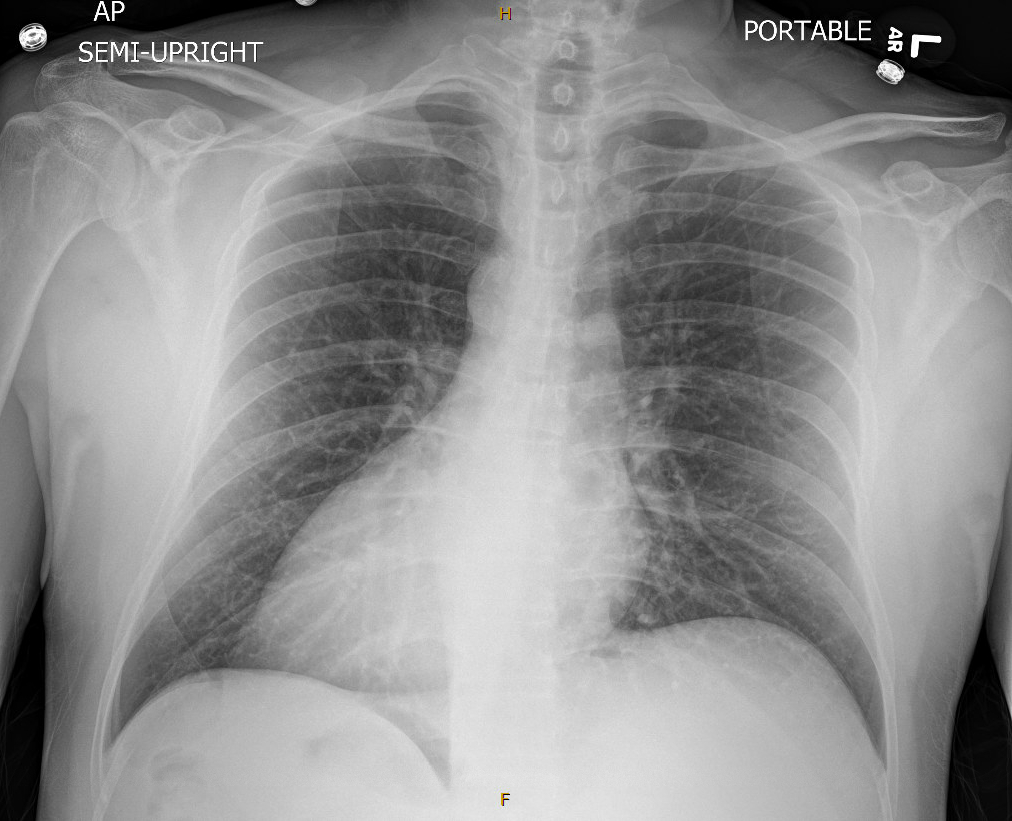

A 49-year-old male with a medical history of dextrocardia, hypothyroidism, dyslipidemia and hypertension was referred to a cardiologist by his primary physician due to a 3-week history of unstable angina. His vital signs were normal, and the physical examination was unremarkable. Electrocardiogram (ECG) showed a prominent S wave in the left-sided leads and a prominent R wave in the right-sided chest leads, suggesting dextrocardia. Although he had a normal echocardiogram and stress test a year ago at a different hospital, due to his symptoms and intermediate-high risk probability of coronary artery disease (CAD), the decision was made to proceed with a cardiac catheterization using a trans-radial approach with a horizontal sweep technique. During the procedure, a 6-French tiger catheter (TIG) was guided into the left coronary sinus and advanced into the left ventricle under fluoroscopic guidance.

The left main coronary artery was widely patent bifurcating into the left anterior descending and left circumflex. The left circumflex had 80% proximal stenosis with minimal luminal irregularities in the mid to distal portion. After guidewire crossing, balloon angioplasty was performed, and a drug-eluting stent was deployed. An intravascular ultrasound was also performed, which was negative for vessel dissection. There were no post-procedure complications, and the patient was discharged on beta blockers and dual antiplatelet agents.